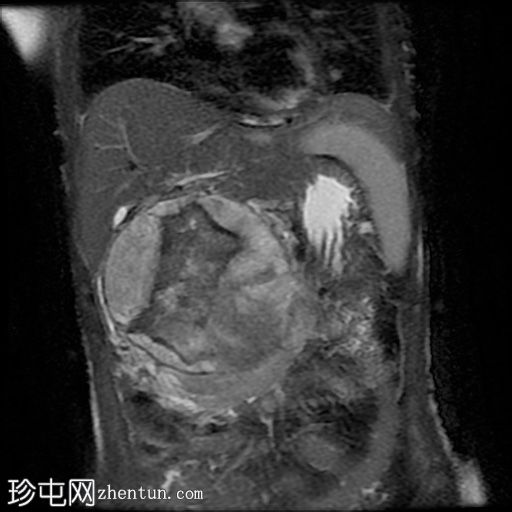

MRI

冠状位

T2加权像

冠状位T2加权像

病灶在T2加权像上呈不均匀高信号,内部区域信号强度不一。

MRCP显示胆总管正常,无胆管扩张或梗阻征象。

主胰管未见,可能由于肿块压迫/取代所致。

病例讨论

影像学检查显示肝下/上腹部存在一个边界清晰、以实性为主的异质性肿块,对邻近结构造成压迫,但脂肪间隙保持完整,且未见明确的血管侵犯,这些特征符合实性假乳头状上皮肿瘤(SPEN)的诊断。

胆道系统和上游胰管未见扩张,这是该生长缓慢的肿瘤的显著特征。

行手术切除,活检证实为SPEN。